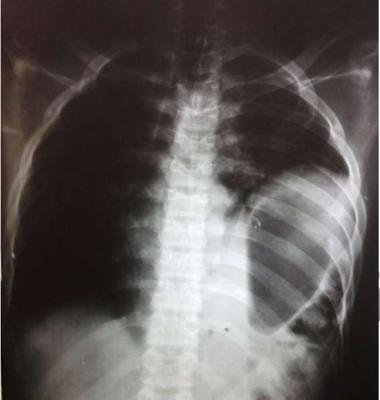

Paciente vítima de atropelamento apresenta-se com redução do murmúrio vesicular a esquerda, estável hemodinamicamente, consciente, orientado e com escoriações abdominais. A radiografia de tórax na sala do trauma é a que se segue: (VER IMAGEM). A Conduta mais adequada é: